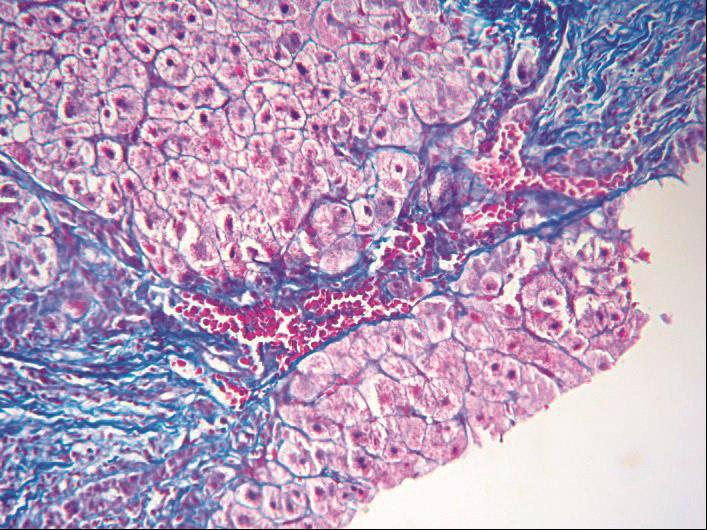

窦周纤维化明显加重,HSC增生,大量细胞外基质形成,包括Ⅰ型、Ⅲ型、Ⅳ型胶原,弹力纤维,纤维粘连蛋白(FN),层粘连蛋白(Ln)等非胶原糖蛋白及多种蛋白多糖(PG),被围绕的肝细胞成片萎缩,甚至消失,形成片状纤维网或纤维间隔(图4-3-4)。重度窦周纤维化常致肝小叶结构紊乱。

图4-3-4 酒精性肝病

酒精性肝纤维化,广泛肝血窦周围纤维化,纤维间隔形成,小叶结构紊乱(Masson染色)